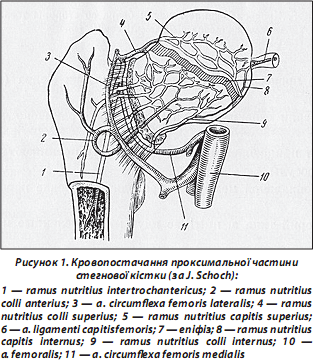

За останні десятиліття докорінно змінилося ставлення до лікування хворих літнього віку з переломами проксимального відділу стегнової кістки. Але проблема хірургічного лікування хворих з переломами, які виникли на фоні структурних порушень кісткової тканини, залишається складною щодо вирішення. Складнощі зумовлені анатомічними особливостями ділянки перелому, його характером і збереженістю кровопостачання. Відомо, що головним джерелом кровопостачання є внутрішня артерія, що огинає шийку стегнової кістки, гілки якої розділяють на 2 групи: медіальна і задньолатеральна. Зовнішня артерія, що огинає шийку стегна, також бере участь у кровопостачанні суглоба. Від неї відходить передня група судин. Ці три групи є основними і постійними (рис. 1).

З боку тазу головка живиться через артерію власної зв’язки головки стегна, що є непостійною, і з віком її роль значно зменшується. Гілки цієї артерії закінчуються біля початку головки у формі петлі і проникають у периферичний шар головки. На жаль, функціональна здатність їх після перелому сумнівна.